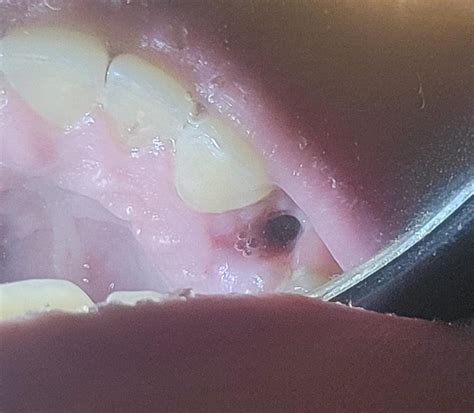

• Is This Healing Good? : R/dentalschool

Tooth extraction : r/DentalSchool